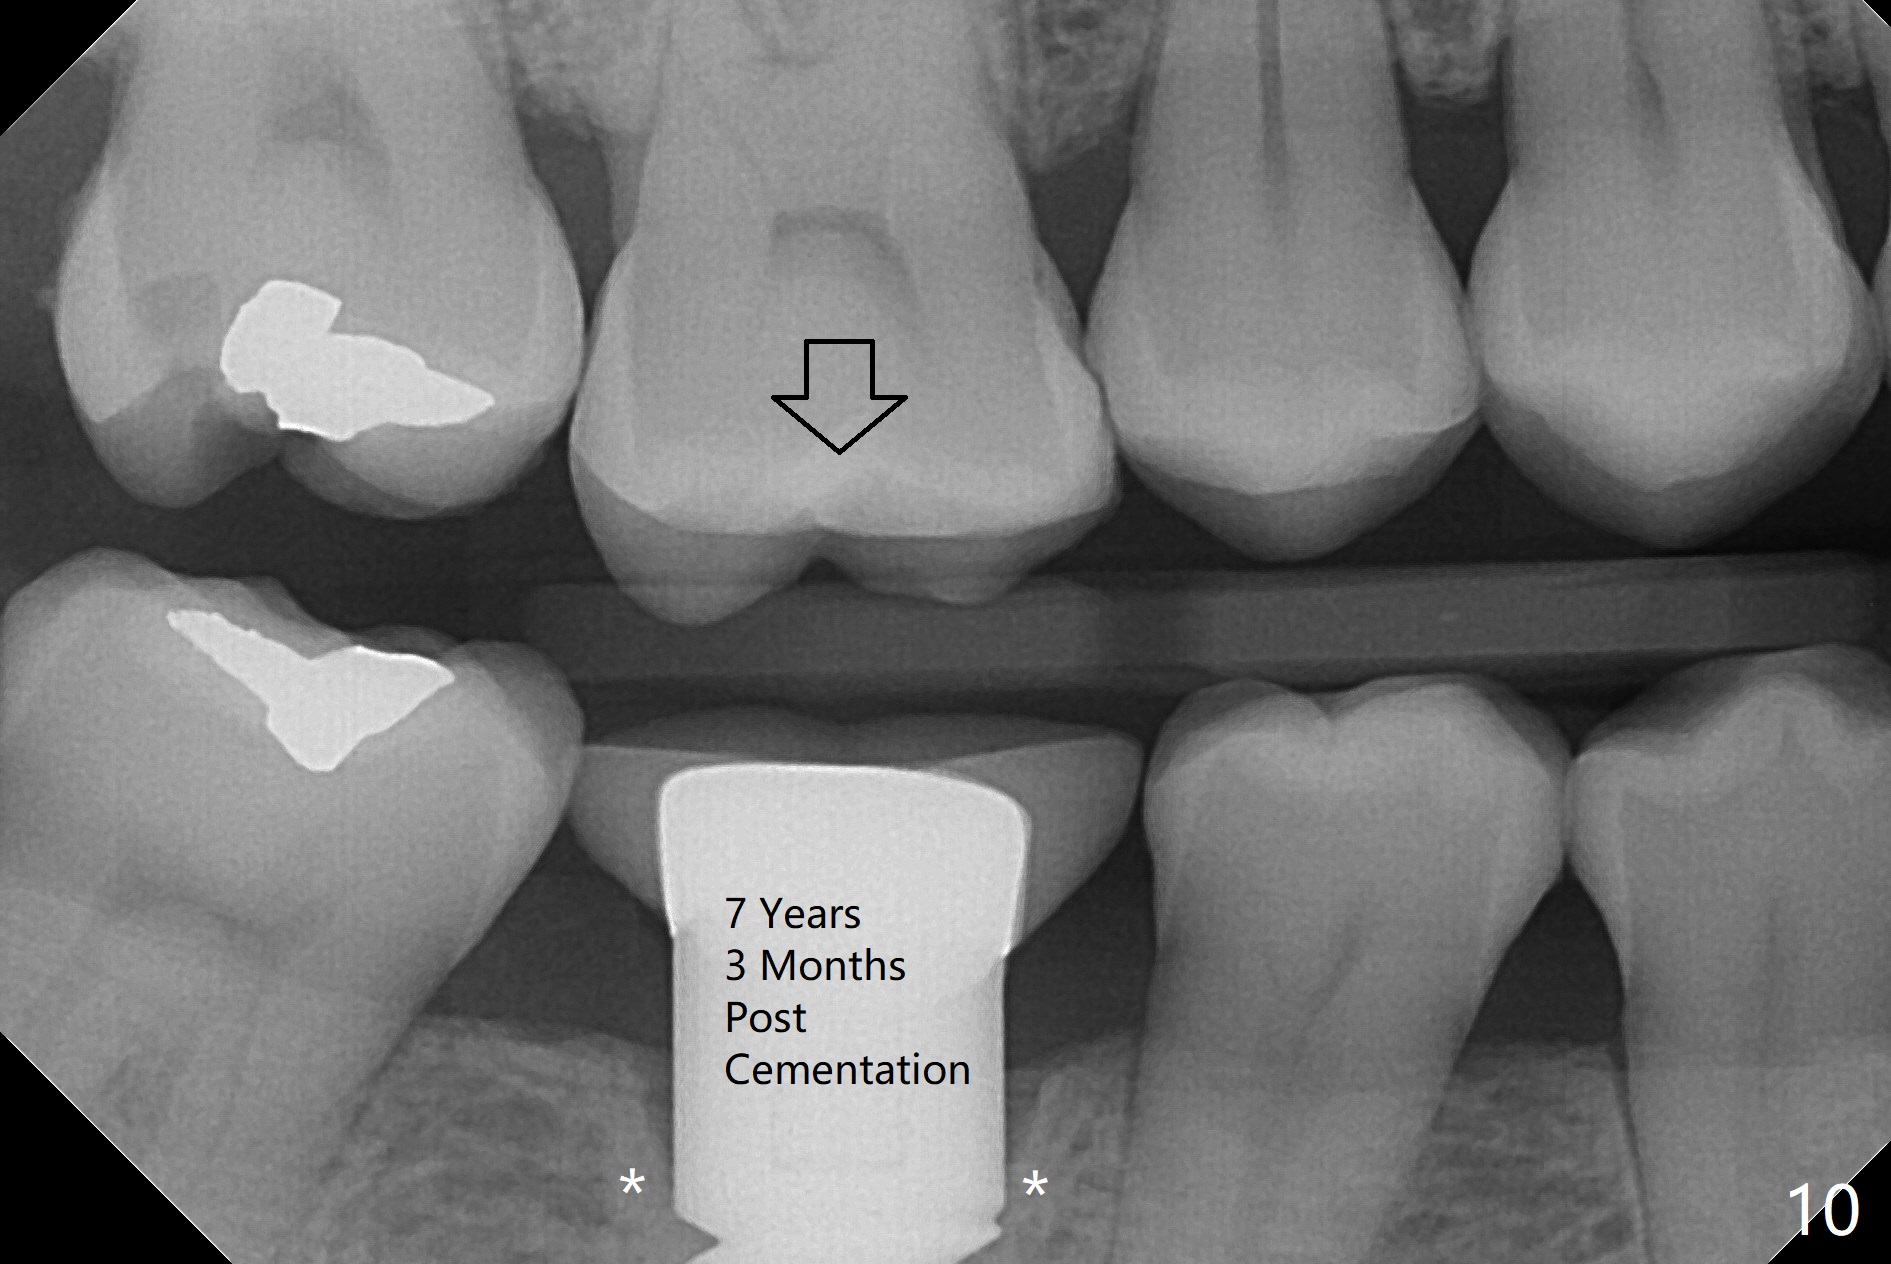

Fig.6-8 show images taken 6, 21 and 34 months post cementation. Bone remains stable 6 years postop (Fig.9).

Metal exposure of the PFM crown (Fig.5,8) is associated with supraeruption of the opposing tooth (Fig.10 arrow). Increased bone density around the coronal portion of the implant 8 years 2 months post cementation (Fig.11 *) suggests bruxism, which is related to distal marginal porcelain chip (^). There is no food impaction with a new crown (Fig.12).